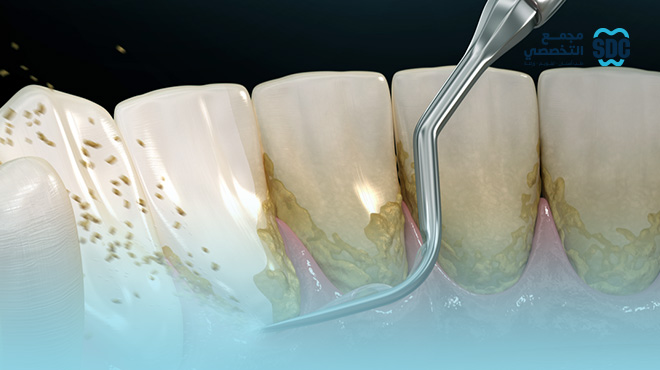

يعتبر من أكثر الخيارات الشائعة التي تهدف إلى التخلص من الجير والبلاك المتراكم على سطح الأسنان وحول اللثة باستخدام أدوات يدوية وأجهزة خاصة. هذا النوع فعالة للوقاية من التسوس ويحافظ على صحة الأسنان بصورة عامة.

في الحالات التي يعاني فيها المريض من أمراض اللثة وتراكم الجير تحت خط اللثة، يشمل تنظيف جذور الأسنان وإزالة الرواسب العميقة، مما يعمل على علاج التهابات اللثة ومنع تفاقم المشاكل في المستقبل.

إزالة الجير والبلاك: يتم استخدام أدوات يدوية وأجهزة بالموجات فوق الصوتية للتخلص من الجير والبلاك تحت سطح الأسنان وخط اللثة " الأماكن التي يصعب الوصول لها بفرشاة الأسنان".